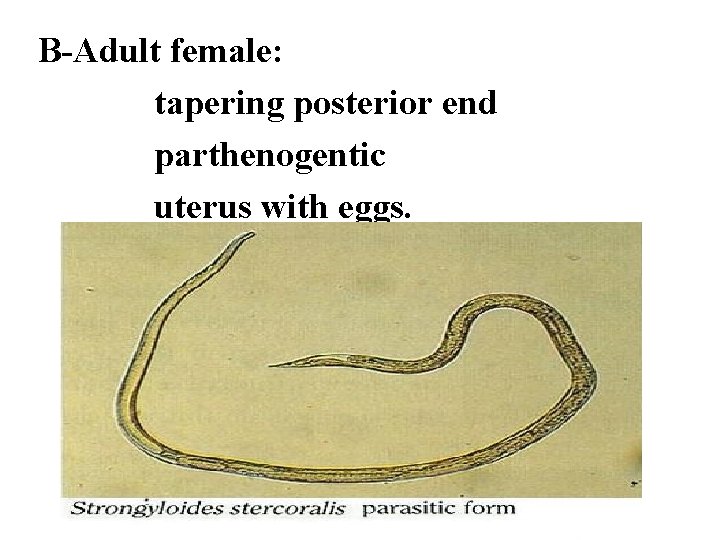

B-Adult female: tapering posterior end parthenogentic uterus with eggs.